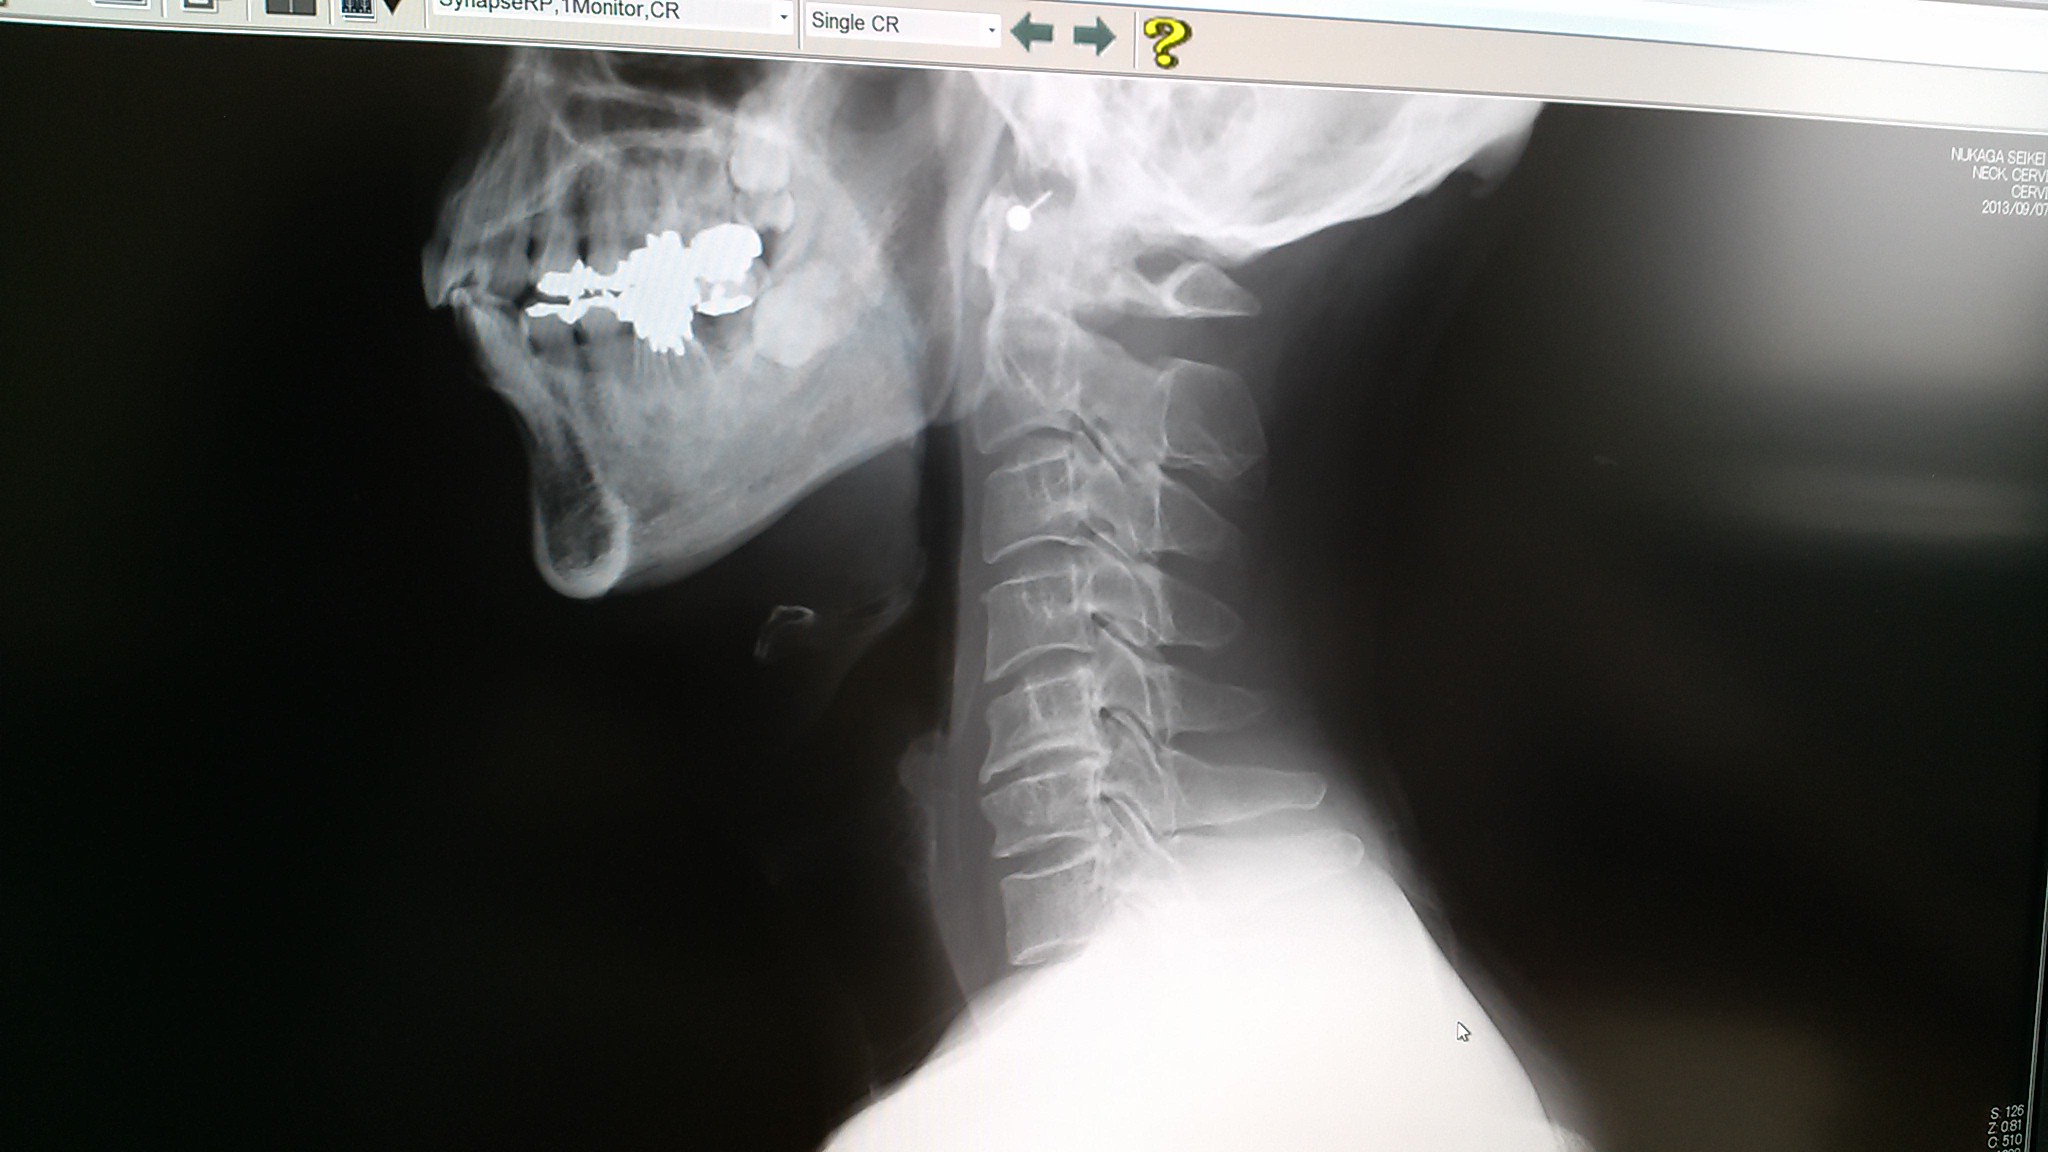

レントゲンを撮ってみると

6番目の椎骨が変形してるとの事。

レントゲンを撮る前はヘルニアを疑ったらしいが

レントゲンを観れば神経根症だと分かるようだ。